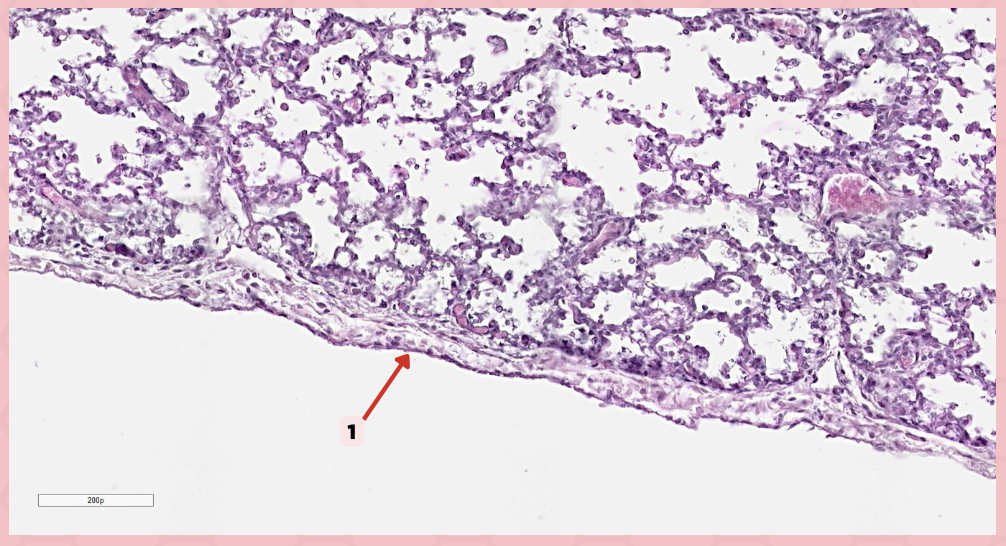

Simple squamous epithelium (Mesothelium)

The surface related to the pleural cavity is in line with what type of epithelium?

Visceral pleura

Identify the structure labeled as 1.

Visceral Pleura

What type of pleura is a thin layer of connective tissues that borders on the outside by mesothelium?

Simple Squamous Epithelium

What epithelium lines the red arrow?

Mesothelium

Identify the structure labeled as 1.